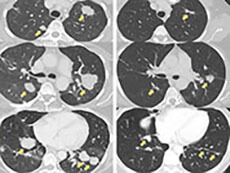

‘Unexpected’ Vulnerability Creates Treatment Opportunity in Aggressive Type of Lung Cancer

A new study has identified a potentially critical vulnerability in lung cancers that have mutations in the KRAS gene, and showed that a drug already under study may be able to exploit it.